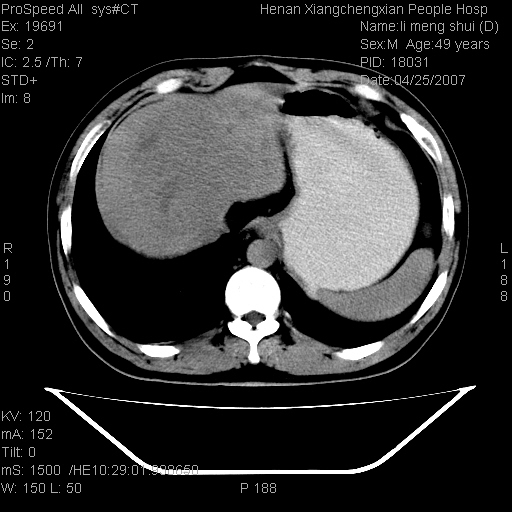

| 患者,男,49岁, 腹疼伴恶心\\呕吐20天,20天前无明显诱因出现右上腹部疼痛,钝疼,无放射,伴恶心\\呕吐,不伴发热.患者不愿增强. b超:肝脏右叶实性占位. ct:肝脏右叶可见一巨块状圆形低密度影,大小约93mm*84mm,其内可见点状高密度影,胆囊、胰腺、脾脏大小、形态及密度未见异常,腹膜后间隙未见肿大淋巴结影。 印象:肝脏右叶巨大肿块,性质待定,建议增强并穿刺活检进一步确诊。 ct平扫: ![]() ![]() ![]() ![]() ![]() ![]() ![]() ![]() ![]() ![]() ![]() ![]() ![]() ![]() ![]() ![]() ![]() 肝脏右叶肿块ct引导下穿刺活检术 患者于16时05分仰卧于ct检查台上,首先行肝脏ct扫描确定进针位置、深度、角度。在局麻下行ct引导下肝脏右叶肿块穿刺活检术。常规消毒、铺巾、局麻。在ct引导下使活检针经右侧腋中线、第9肋间隙垂直胸壁进针90mm,针头进入病变预定位置。在病变预定位置多点、多方向抽取小米样病变组织多块,涂片五张送病理检查。术后穿刺点局部无出血,未出现腹腔积液等并发症。术中及术后患者生命体征稳定,手术于17时10分成功完成。患者安返病房。 穿刺片 ![]() ![]() ![]() ![]() ![]() ![]() ![]() ![]() ![]() ![]() ![]() ![]() ![]() ![]() ![]() ![]() 病理结果肝细胞癌 ![]() 原贴地址:http://www.radinet.com.cn/forum_view.asp?forum_id=4&view_id=24130 ok |